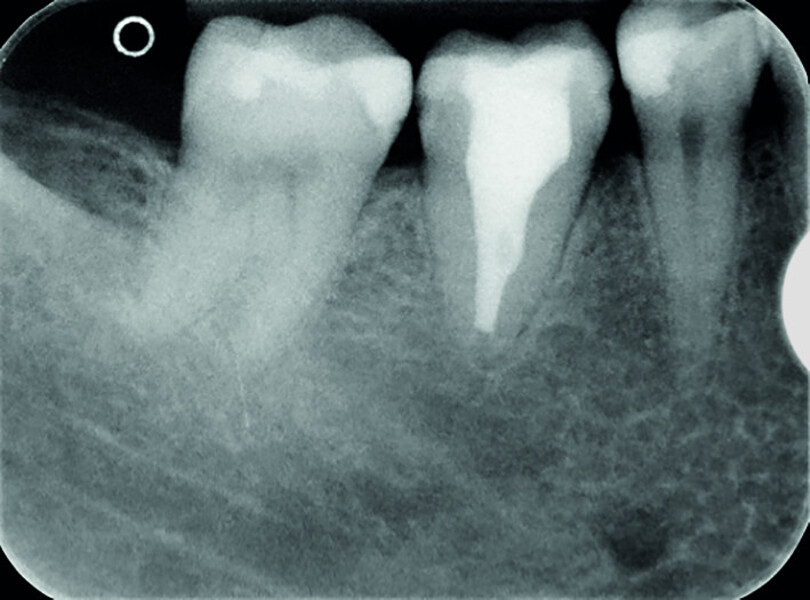

Fig. 19a: Radiographs: Pre-op periapical.

Fig. 19b: Radiographs: Immediately after transplantation.